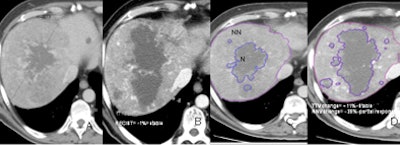

| Evaluation of therapy response in a 52-year-old living male with HCC showing a good clinical response to antiangiogenic therapy. Baseline CT scans (A,C) and six months post-treatment CT (B,D) show stable disease according to existing RECIST and TTV criteria but a partial response according to proposed NNV criteria (-28% reduction on NNV). |

| Tumor viability quantification begins with segmentation to estimate total tumor volume and non-necrotic tumor volume. Structure segmentation, extraction, and feature computation are performed for semiautomated/computer-aided detection (CAD) quantification algorithm. Tissues within a defined range of HU values are defined and then margins are outlined, including outer tumor boundaries for TTV; Necrotic portion outlines (10-35 HU). All images courtesy of Dr. Dushyant Sahani. |